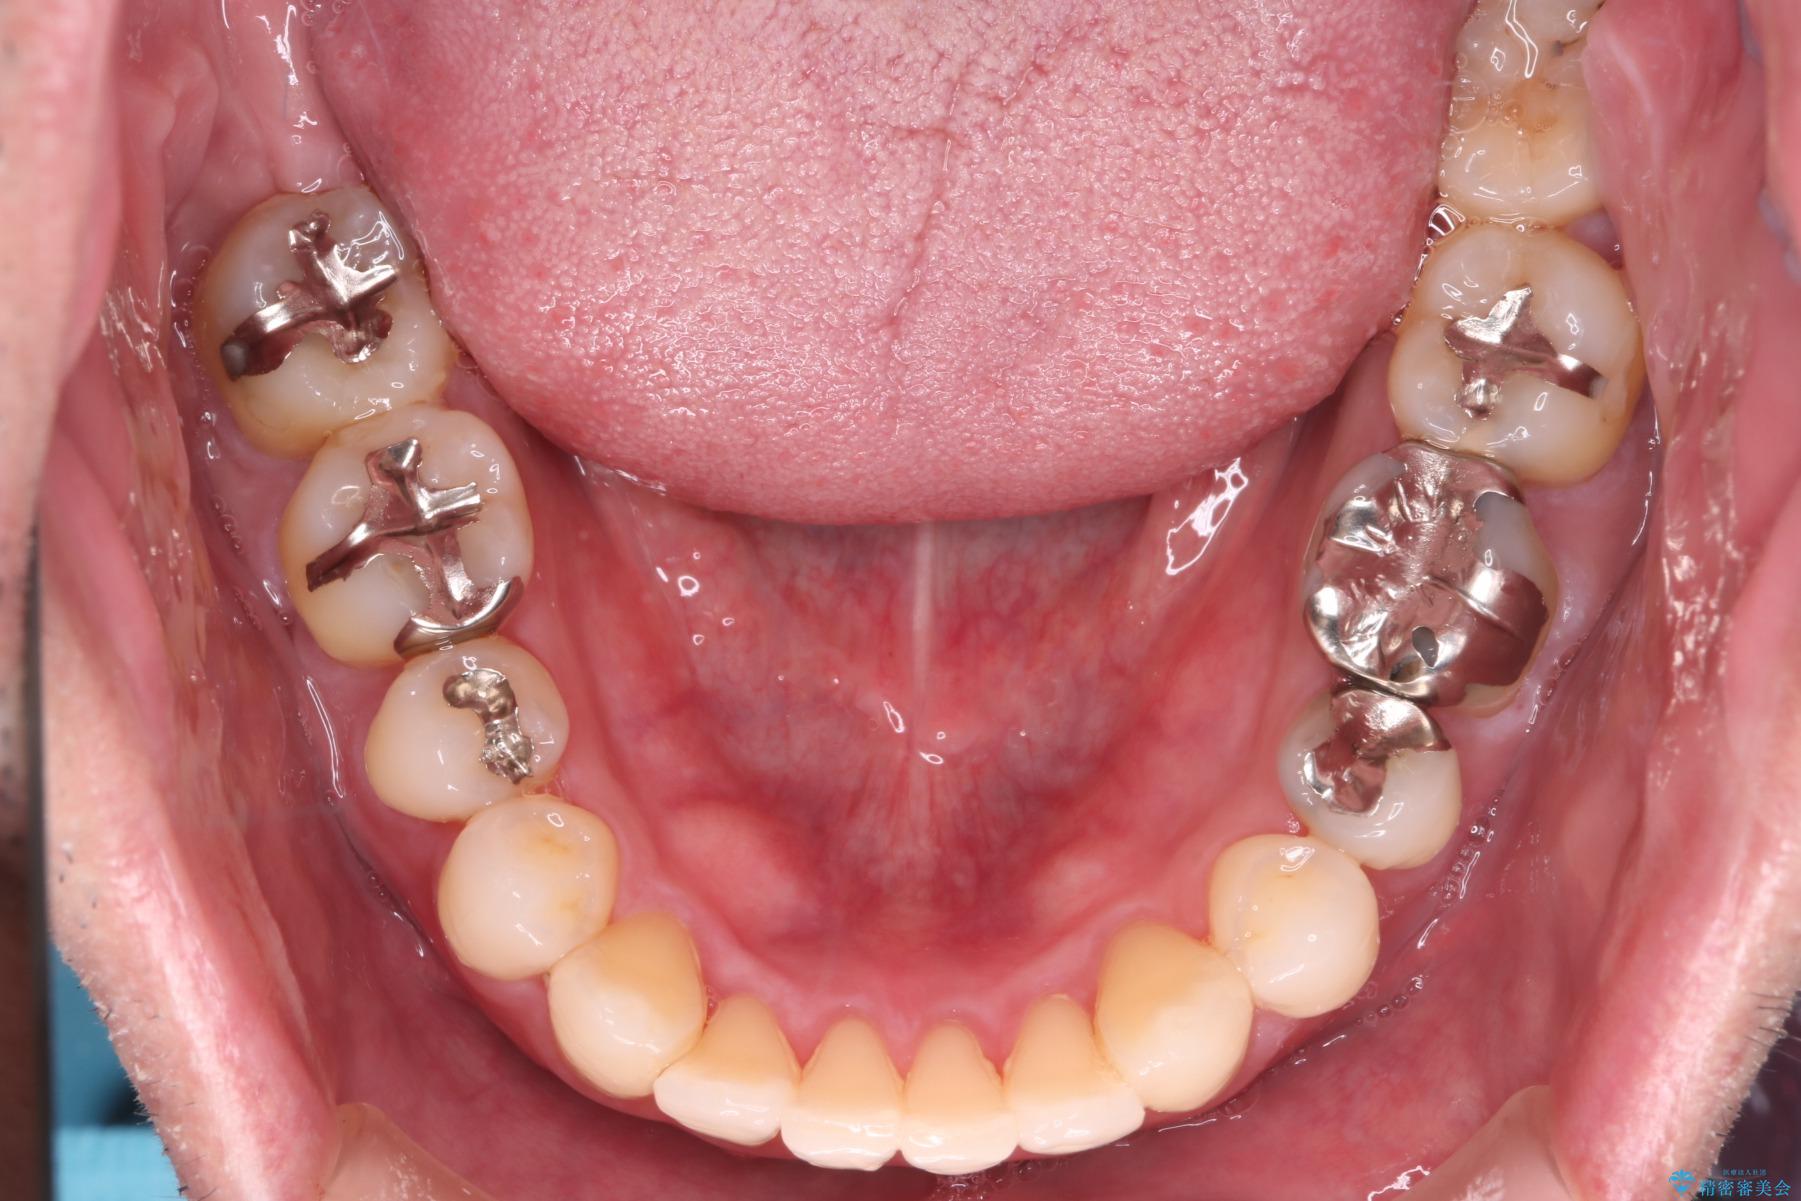

【メタル装置】1本のみ抜歯してワイヤー矯正

- 右上2番目の歯が舌側転位していることと前歯の叢生(がたつき)を主訴に来院されました。

右上の犬歯が初診時よりかなり歯根露出しており、矯正の力をかけるとさらに歯根露出するリスクがあるため、右上の2番目の歯を前に出すためにも

右上の犬歯を抜歯して歯並びを整える治療計画を立てました。

下のがたつきをとるために、IPR(歯と歯の間を削る処置)も行って歯を並べていきます。